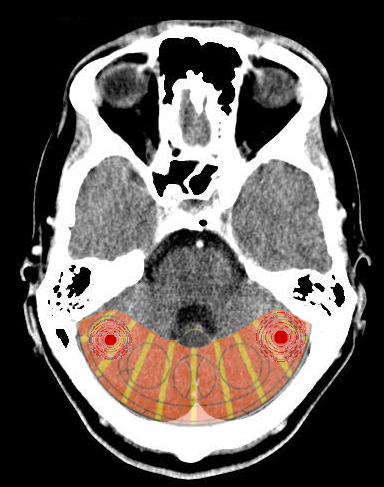

- Relè cerebrali: Due SBS a livello cerebellare

- Manifestazione: Appianamento emozionale, "anestesia". "Morte emozionale", assenza di qualsiasi emozione, desiderio e stimoli. Eventuali azioni non convenzionali. Sensazione di essere morto dentro, pietrificato. Un muro di gomma, tutto mi rimbalza.

Comportamento antisociale. Non riconoscere i diritti degli altri. La persona si mostra fredda e solitaria.In caso di doppia preoccupazione nel nido (ghiandole mammarie destra e sinistra): Voler aiutare e proteggere tutti, voler nutrire tutto il mondo. "Sindrome di Madre Teresa" o della "Supermamma", del "buon samaritano".

Le ragazzine che hanno questa costellazione, all'arrivo della pubertà (che normalmente è in relazione con l'ipofisi che produce la prolattina) presentano un volume mammario superiore al normale, durante lo sviluppo fisico. Se si combina con la megalomania del miocardio, vogliono aiutare tutti e a tutti i costi e si presentano come donna meravigliose e materne che si preoccupano sempre di tutti. - Senso biologico: L'individuo fortemente minacciato o attaccato da tutti i lati entra in uno stato di "fare il morto" mentre il pericolo è presente, in stato di emergenza (nessuno attacca un morto).

Questa costellazione del Cervelletto produce uno stato più o meno accentuato di una forma particolare di "anestesia". La persona vede ogni minimo dettaglio, non gli sfugge nulla, anche di fronte a situazioni o fatti molto gravi. Per lui "tutto va bene". Sono dei mediatori molto efficaci e sebbene siano continuamente aggrediti violentemente, continuano con un sorriso.

Il vantaggio di questa situazione in cui "fa il morto" è che permette di mantenere, in situazioni disastrose, il sorriso e di non farsi schiacciare dagli eventi. Lo svantaggio sarà che non sentendo dolore emotivo, continuerà a sbattere contro lo stesso ostacolo, sorprendendosi poi di avere dolore o sintomi gravi.

Nella pratica clinica queste persone saranno quelle che hanno i sintomi peggiori e le condizioni più gravi, avendo avuto recidive conflittuali per lungo tempo (essendo anestetizzati). - Connessioni con il DSM: Questo quadro è compatibile con il Disturbo da Stress Post-traumatico, con il Disturbo reattivo dell'attaccamento. Anche nei Disordini Neuro-Cognitivi si riscontrano le manifestazioni di questa costellazione.